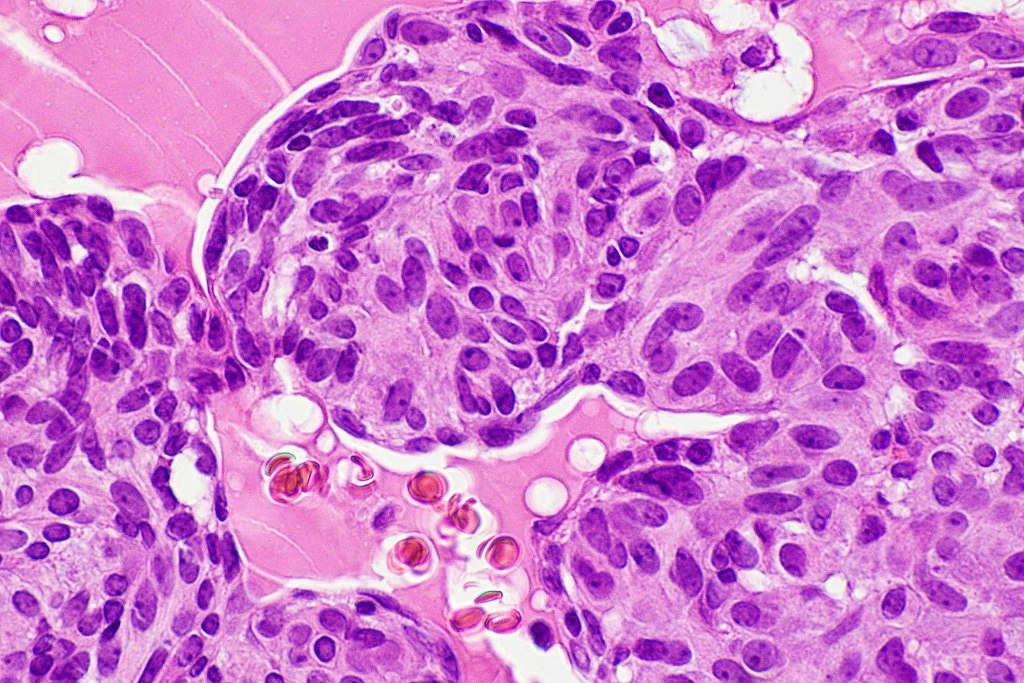

•Mucinous carcinoma is characterized by epithelial islands dispersed in a rich mucinous stroma

•Eosinophilic cytoplasm & small vesicular nuclei

•Mitoses scanty to absent

•No significant pleomorphism

•+/- decapitation secretion

•EMPSGCa– multiple nodules of uniform epithelial cells with vesicular nuclei & small nucleoli

•In situ component sometimes evident

•Cyst formation sometimes evident

•Papillae & cribriform pattern sometimes evident

•+/- apocrine decapitation secretion